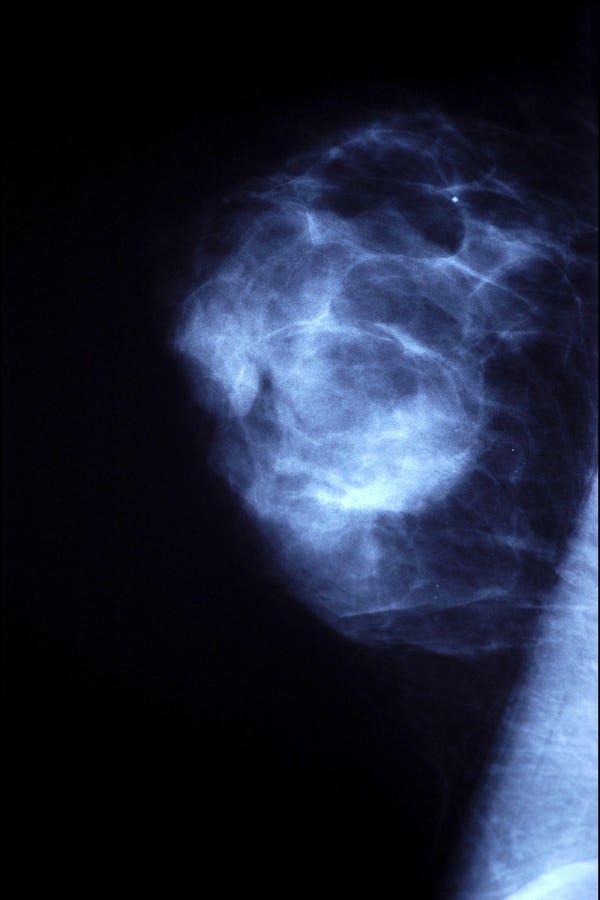

Both men and women usually undergo the same diagnostic tests when trying to identify breast cancer. For example, men or women who feel a lump in their breast will usually go on to get a mammogram, which are low-dose x-ray images geared toward detecting any abnormalities in the breast such as suspicious masses or lesions.

If an abnormality is present on a mammogram, additional studies and procedures could include an ultrasound, MRI or even a biopsy to confirm a specific diagnosis.